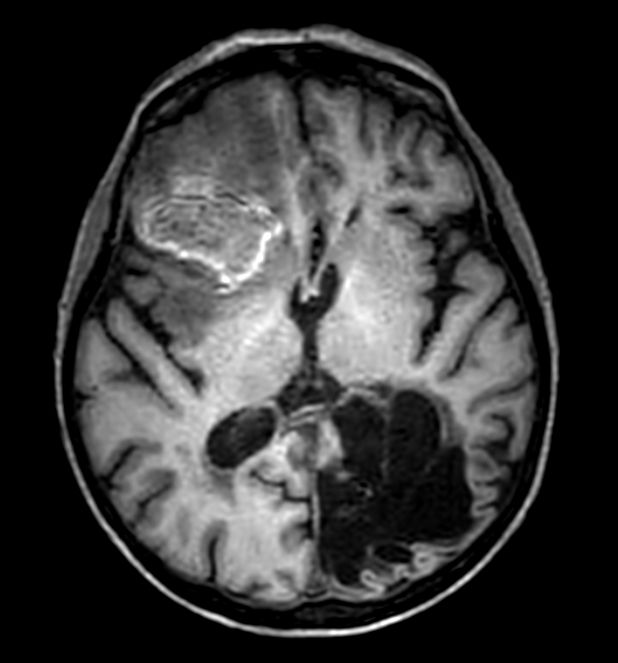

Sagittal 3D T1w FFE

3D T1w FFE (axial reformat)

3D T1w FFE (coronal reformat)